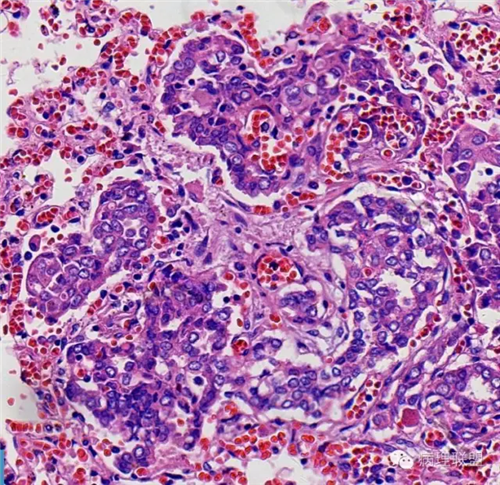

肺的

不仅仅是肺水肿